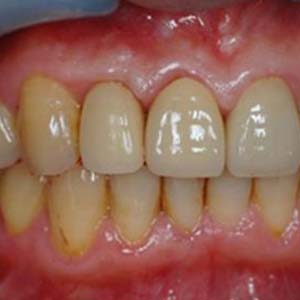

"4個月骨整合完成後,利用植牙支台齒,製作全瓷冠,恢復外觀"

裝戴正式假牙

Before

After